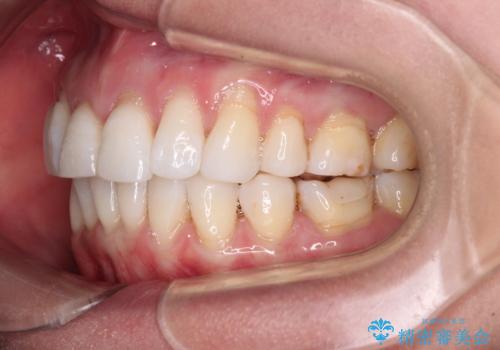

- 上の前歯の出っ歯を治したいとのことで来院された患者様です。

後戻りによる再矯正というもともあり、インビザラインを希望されていました。

上顎の歯は後方移動とIPR(歯と歯の間を削る)によって口元が引っ込むように、下顎は歯列全体の拡大とIPRによって上顎とバランスよく咬み合うように設計し、インビザラインにより治療を行うこととしました。

治療を開始して暫くして、勤務先から2年以上帰国することができず、それまでの移動がほとんど後戻りしてしまい、帰国後に再度後戻りをリカバリーするための治療を行うこととなりました。

5年以上の治療期間がかかりましたが、気になっている部分を改善することができました。